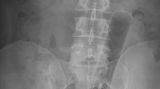

Die Webseite radiopaedia.org zeigt, welche Dinge Ärzte auf Röntgenbildern schon entdeckt haben. Die Aufnahmen wirken skurril und erschreckend zugleich und machen deutlich, wie weit die eingeführten Dinge bereits in den mescnhlichen Darm vordringen können.

Aber Glück im Unglück für die Patienten: Die Gegenstände können meist ohne Operation entfernt werden. Sehen Sie hier einige der spektakulärsten Röntgenaufnahmen. Da runzeln selbst Chirurgen die Stirn.